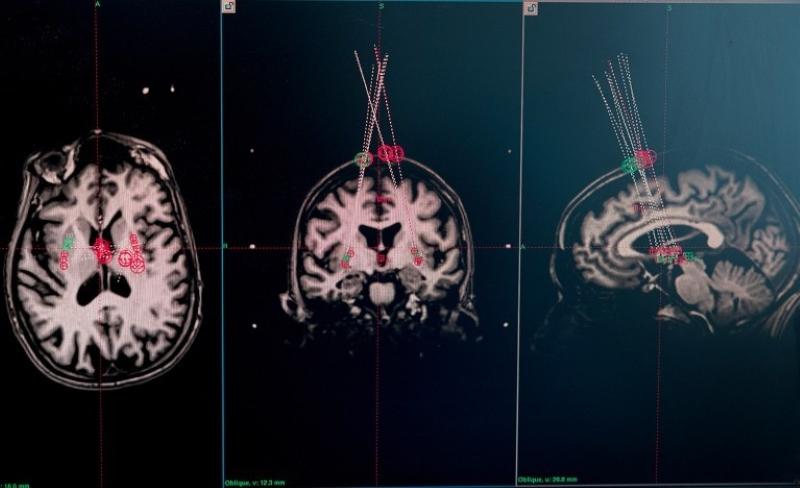

关于癫痫的研究同样值得关注。在美国神经元治疗公司开展的临床试验中,外科医生借助干细胞疗法,将干细胞整合到15名癫痫患者的神经回路中。移植一年后,其中两名参与者严重癫痫发作的频率几乎降至零,且效果已经持续了两年。其他大多数参与者的癫痫发作频率也显著降低。该公司报告称,这一疗法没有明显副作用,也没有造成认知损伤。基于上述效果,包括神经元治疗公司在内的团队打造的“有效干细胞疗法”,也被《麻省理工技术评论》评为2025年“十大突破性技术”之一。